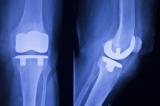

Британский ученый использовал космические технологии для создания антигравитационной беговой дорожки. Она поможет людям преодолеть страх повторной травмы и повысит уверенность после операций на колене, пишет The Indian Exress...